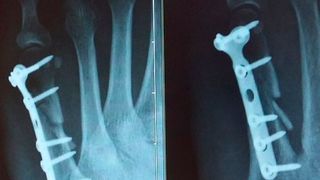

Mit ihrem Bioprinter gelang es den Forschern, Knochenkonstrukte für die Gewebeersatzforschung zu drucken. Die 3D-Strukturen waren durchblutet und vital wie natürlicher Knochen.